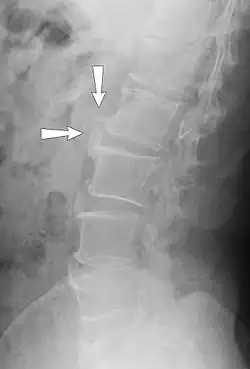

Farmers with long-term exposure to whole body vibration and mechanical shocks have a higher prevalence of back pain (compared to those not exposed to vibration), and the prevalence increases with vibration dose.[10] Long-term exposure affecting the whole body leads to spinal degeneration (spondylosis) and increased risk of low back pain.[11][12]